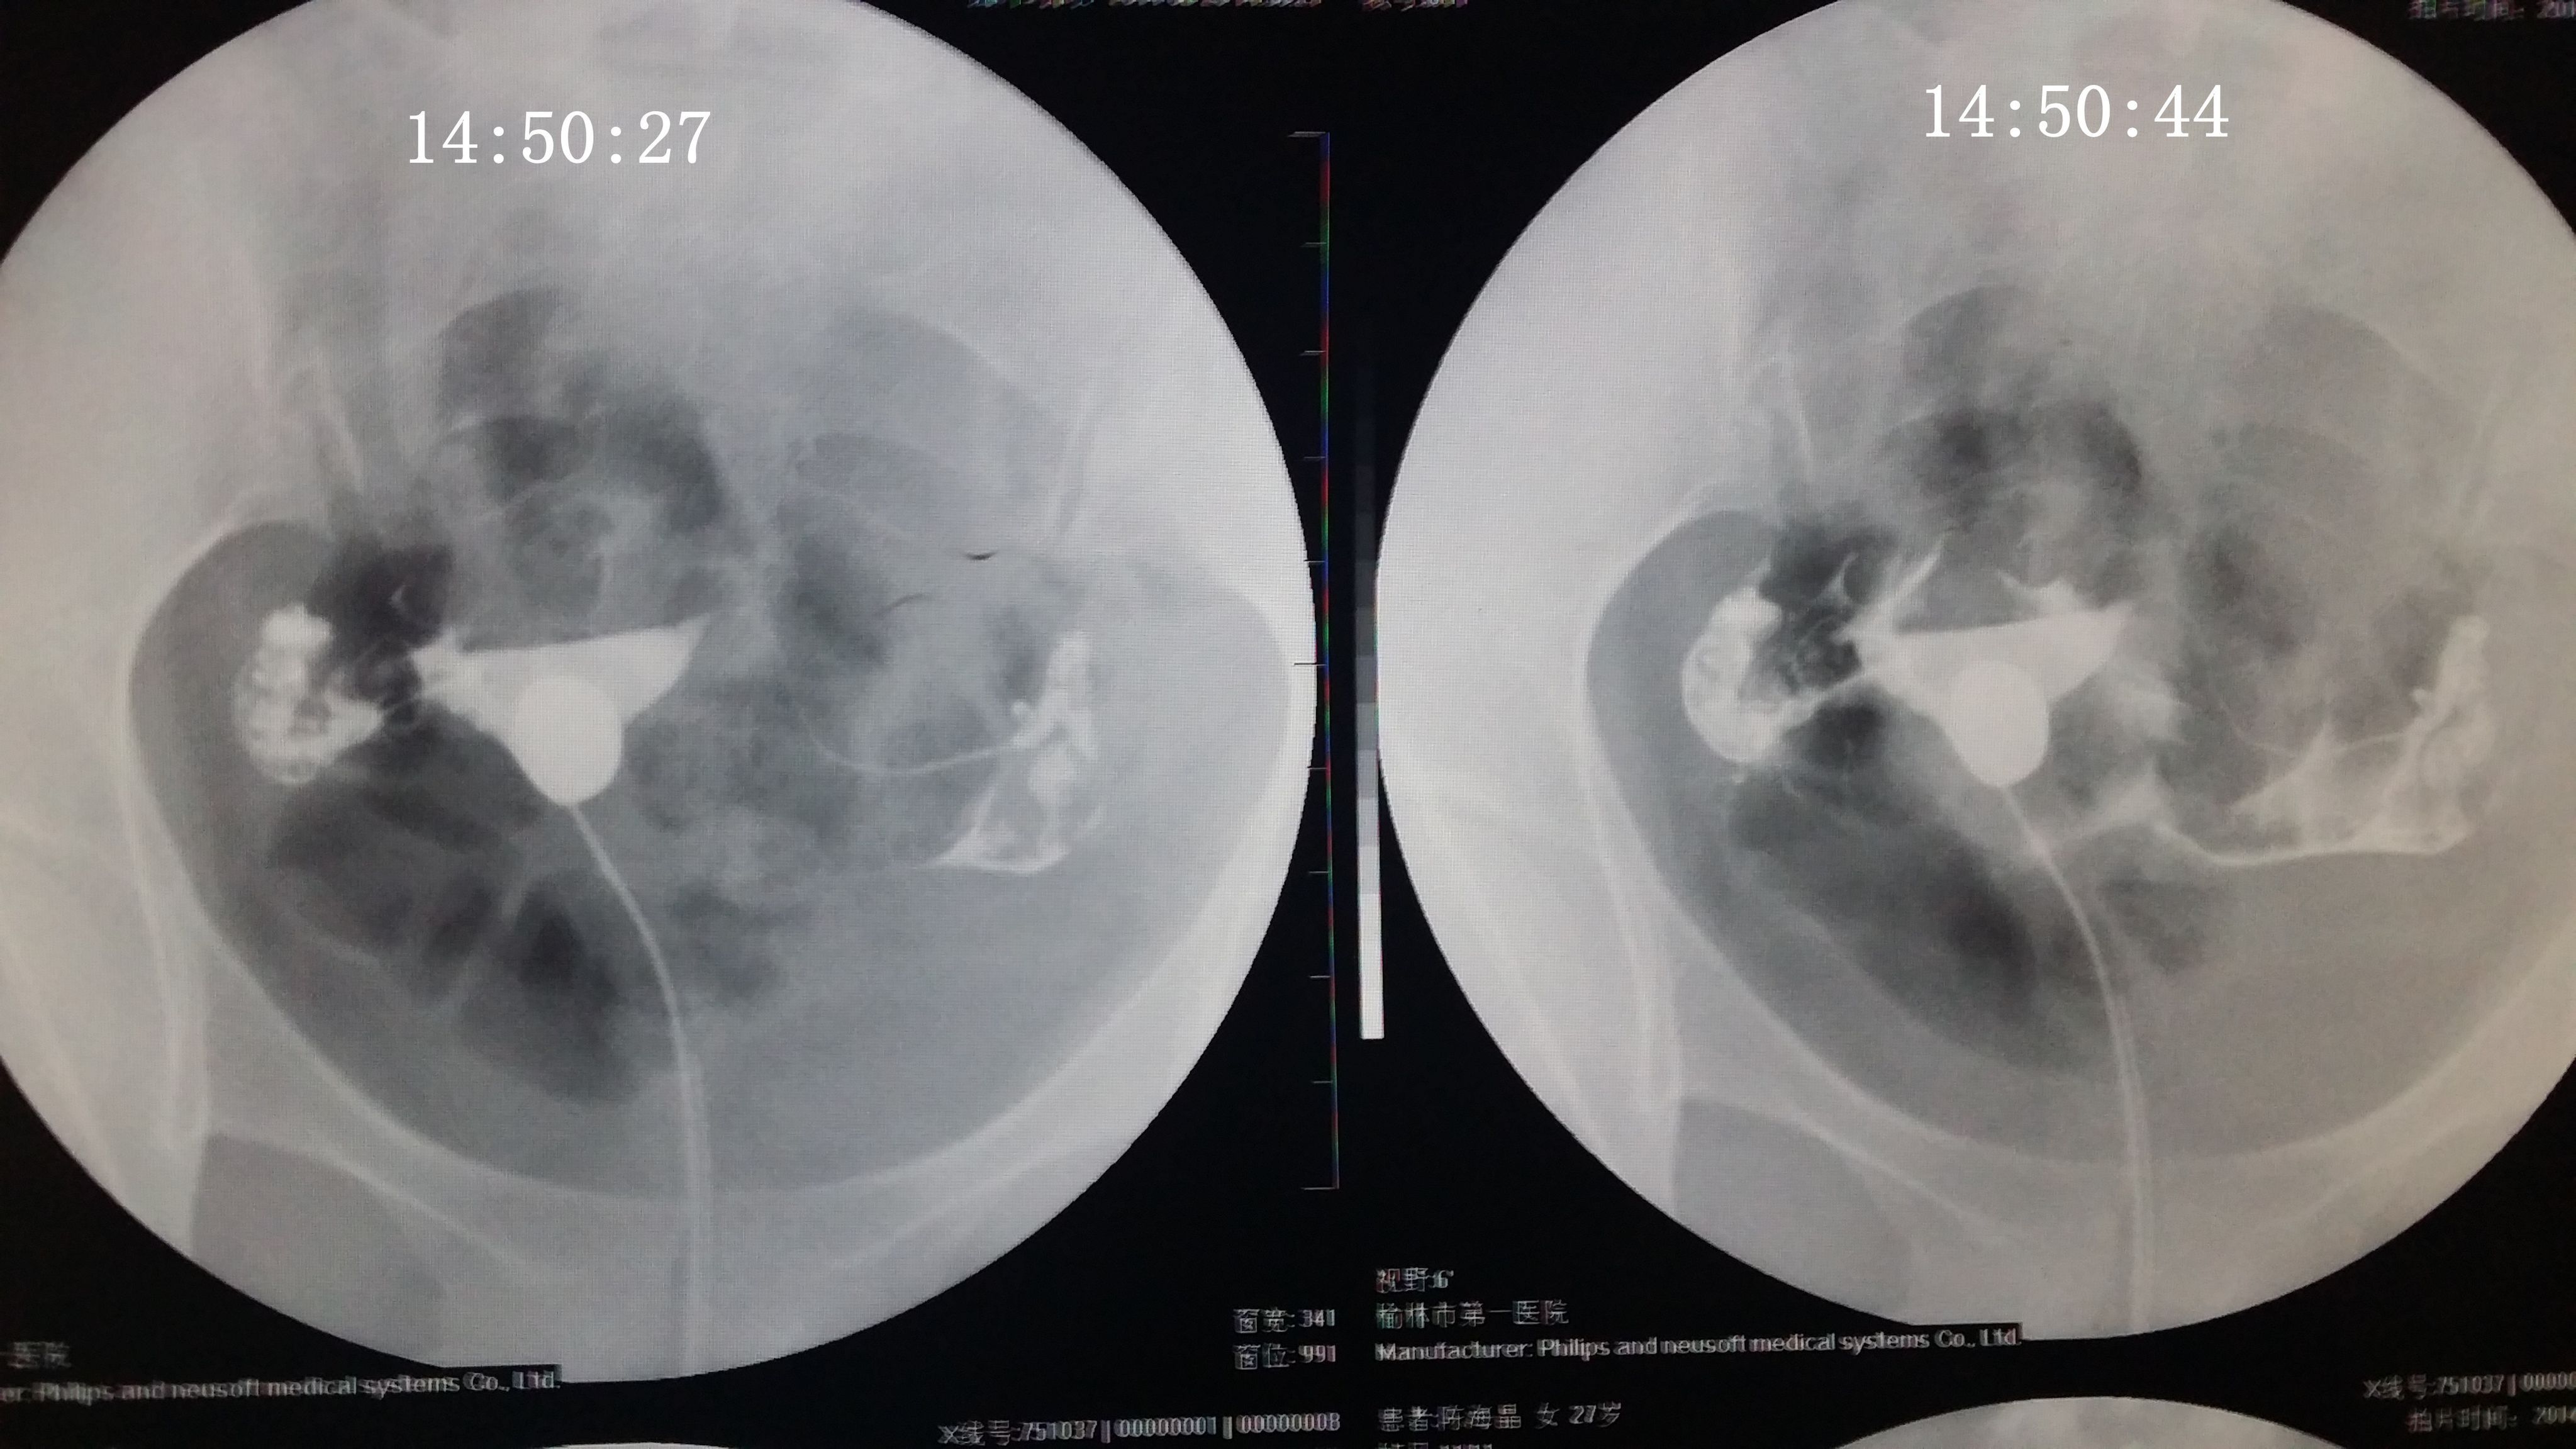

请专家帮我分析下我的造影片 医生诊断说是没问题,只是右侧输卵管伞部有点弯曲不直,说左侧通着可 以自然受孕,不知道会不会有错,之前在其他医院没做造影直接做的通液,说是阻力很大,堵的厉害后过几个月在另一家医院做的这个造影片。(另之前有过盆腔积液,但已经治疗好了} 造影都好几天了右侧一直觉得酸痛的,是不是又发炎了啊,吃药可以吗? 点击展开 匿名用户 2014-09-04 20:09 为您推荐: 其他回答 你好,这个还好的啊,这个不是已经通过了里面,这个这样就是不会有什么事情的 的哦 生活还在继续66 2014-09-05 14:56 相关问题 输卵管通而不畅,迂曲右侧上举,请问济南哪个大医院治疗这个专业啊~请有经验的人告诉下~急急急另附造影片 输卵管伞端不通怎么办 如果排了,B超能检测出来吗?B超单上会显示什么?12月22号做的造影,结果是右侧输卵管伞端通而不

以自然受孕,不知道会不会有错,之前在其他医院没做造影直接做的通液,说是阻力很大,堵的厉害后过几个月在另一家医院做的这个造影片。(另之前有过盆腔积液,但已经治疗好了} 造影都好几天了右侧一直觉得酸痛的,是不是又发炎了啊,吃药可以吗?